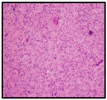

| Histology (diagnosis) | ||||

| H&E | ![]() | ![]() | ![]() | ![]() |

| IHC | ||||

| Ki67 (%) | 50–80 | 20–25 | 15 | 10–15 |

| GFAP | pos | pos | pos | pos |

| p53 | pos | neg | pos | pos |

| EGFR | neg | pos | pos | pos |

| PTEN | pos | pos | NA | pos |

| HIF-1α (%) | 20 | 50 | 50 | 20 |

| Olig2 (%) | 70 | 100 | 10 | 50 |

| Olig2 (%) at relapse | 30 | 50 | NA | NA |